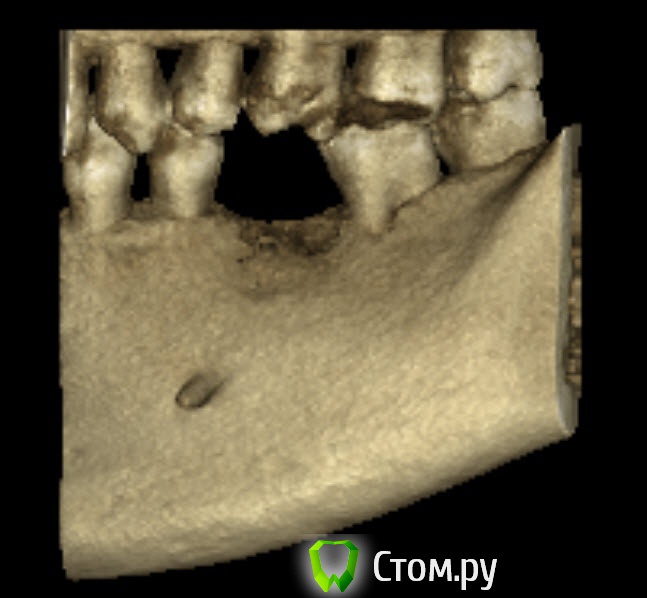

bobrdobr Опубликовано 18 февраля, 2014 Автор Поделиться Опубликовано 18 февраля, 2014 (изменено) Имплант был предложен Semados 4,1*11,5 без костной пластики. судя по фото, скорее всего нужна. От КТ нужен срез горизонтальной плоскости - вид сверху на костный гребень, на 1 мм ниже его вершины. Сейчас попробую. Прикладываю 4 снимка: на уровне гребня (как мне кажется) и на 1,2,3 и мм. ниже. Изменено 18 февраля, 2014 пользователем bobrdobr Ссылка на комментарий

Bier Опубликовано 18 февраля, 2014 Поделиться Опубликовано 18 февраля, 2014 Можно поставить, одновременно добавив немного кости и закрыть мембраной. Кость можно даже взять прямо из того места, куда будет ставиться имплантат, т.е. доп травмы не будет Ссылка на комментарий

bobrdobr Опубликовано 18 февраля, 2014 Автор Поделиться Опубликовано 18 февраля, 2014 Можно поставить, одновременно добавив немного кости и закрыть мембраной. Кость можно даже взять прямо из того места, куда будет ставиться имплантат, т.е. доп травмы не будетБольшое спасибо за мнение! Ровно такой вариант предлагал хирург 3 под винтовой имплант. Правда, он же предложил байкон Что будет, если кость не подсыпать и мембрану не ставить? Ссылка на комментарий

Bier Опубликовано 18 февраля, 2014 Поделиться Опубликовано 18 февраля, 2014 Может и ничего не будет, если широкий диаметр не выбирать и десну подсадить, а может десна немного отойдет вниз через годик-другой. Ссылка на комментарий

bobrdobr Опубликовано 18 февраля, 2014 Автор Поделиться Опубликовано 18 февраля, 2014 Все ясно, благодарю. Диаметр 4,1 мм предлагают (Semados). Нормально для жевательного зуба? Ссылка на комментарий

Bier Опубликовано 18 февраля, 2014 Поделиться Опубликовано 18 февраля, 2014 Тогда подсыпать однозначно нужно, 4,1- стандартная платформа. Лучше сюда ставить тонкую платформу. Неважно какой зуб, они держат нагрузку. Главное чтобы кость была вокруг имплантата. Ссылка на комментарий